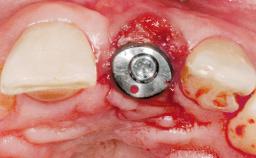

A 42-year-old female patient was referred to our clinic at the School of Dentistry of the University of São Paulo in November 2004, presenting a deficient restoration in the upper left central incisor. The clinical examination revealed no gingival retraction or any signs of gingival inflammation and, therefore, previous periodontal treatment was not considered. The patient presented a high lip line at full smile and a thin tissue biotype. This combination characterized a high-risk situation from an anatomic point of view, which required careful preoperative planning and cautious surgical execution.

Placement Protocol Immediate implant placement

Tooth Site Maxillary incisor or canine

Loading Protocol Immediate

Provisional Implant-Supported Prosthesis Prosthodontic margin < 3 mm apical to mucosal margin Prosthodontic margin < 3 mm apical to mucosal margin